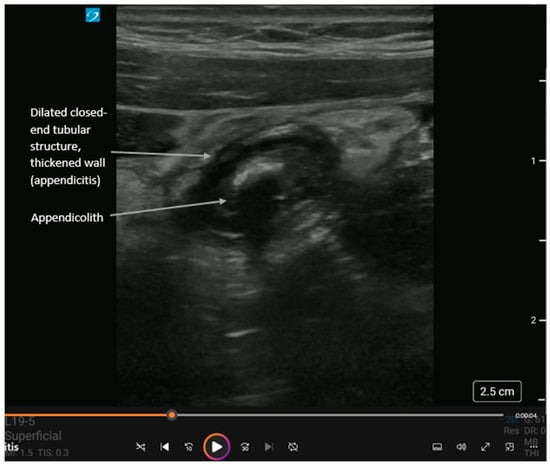

Figure 4.

Short-axis view of acute appendicitis with an appendicolith and dynamic findings in Supplementary Video S4. The appendix is a closed-ended tubular structure usually found in the right lower quadrant of the abdomen. Landmarks for locating the appendix are the psoas muscle laterally and inferiorly, the external iliac vessels medially and inferiorly, and the internal oblique and transversus abdominis muscles anteriorly. In cases of acute appendicitis, the appendix diameter is dilated > 5 mm and non-compressible. Like with diverticulitis, ultrasound shows (i) thickened bowel wall > 3 mm, (ii) hyperemic bowel wall, and (iii) hyperechoic surrounding fat. An appendicolith (hyperechoic circular structure with posterior shadowing) or debris may be visualized within the bowel lumen. Also, complications can include extra-luminal free fluid (anechoic adjacent to the appendix), an abscess (heterogeneous collection adjacent to the appendix), or perforation (disruption of the appendiceal wall with either free fluid or abscess). While operator-dependent, recent meta-analyses report pooled sensitivity and specificity for POCUS diagnosis of appendicitis to be approximately 81% and 87%, respectively, making it a highly effective rule-in tool [19,20,21,22].